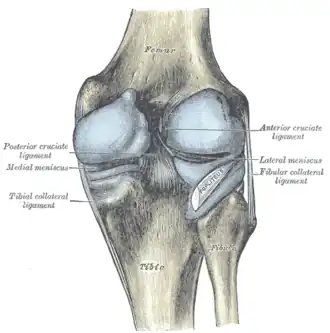

Anatomy

Skeletal components involved in the unhappy triad include: patella, femur, tibia. No muscles are directly involved in this injury, only ligaments; However, strengthening the hip flexor and hip extensor muscles may help alleviate the injury.

The medial collateral ligament, posterior cruciate ligament, anterior cruciate ligament, and lateral collateral ligament are the four primary ligaments of the knee. The medial and lateral collateral ligaments primarily provide support to varus and valgus forces whereas the anterior and posterior cruciate ligaments prevent anterior and posterior translation of the tibia on the femur.[2]

Structures in triad

The classic O'Donoghue triad is characterized by an injury to three knee structures (in order):

- the anterior cruciate ligament

- the medial meniscus (however, lateral meniscus[1] injuries are more commonly seen among athletes, leading to the definition of the O'Donoghue triad most commonly used today.) [3][4][5]

- the medial collateral ligament (or "tibial collateral ligament")

The anterior cruciate ligament

The anterior cruciate ligament is one of the four crucial ligaments in the knee. It originates from the lateral condyle of the femur and goes to the intercondyloid eminence of the tibia. Its function is to provide stability in the knee and minimize stress across the knee joint. It also restrains excessive forward movement in the leg and limits rotational movements in the knee.